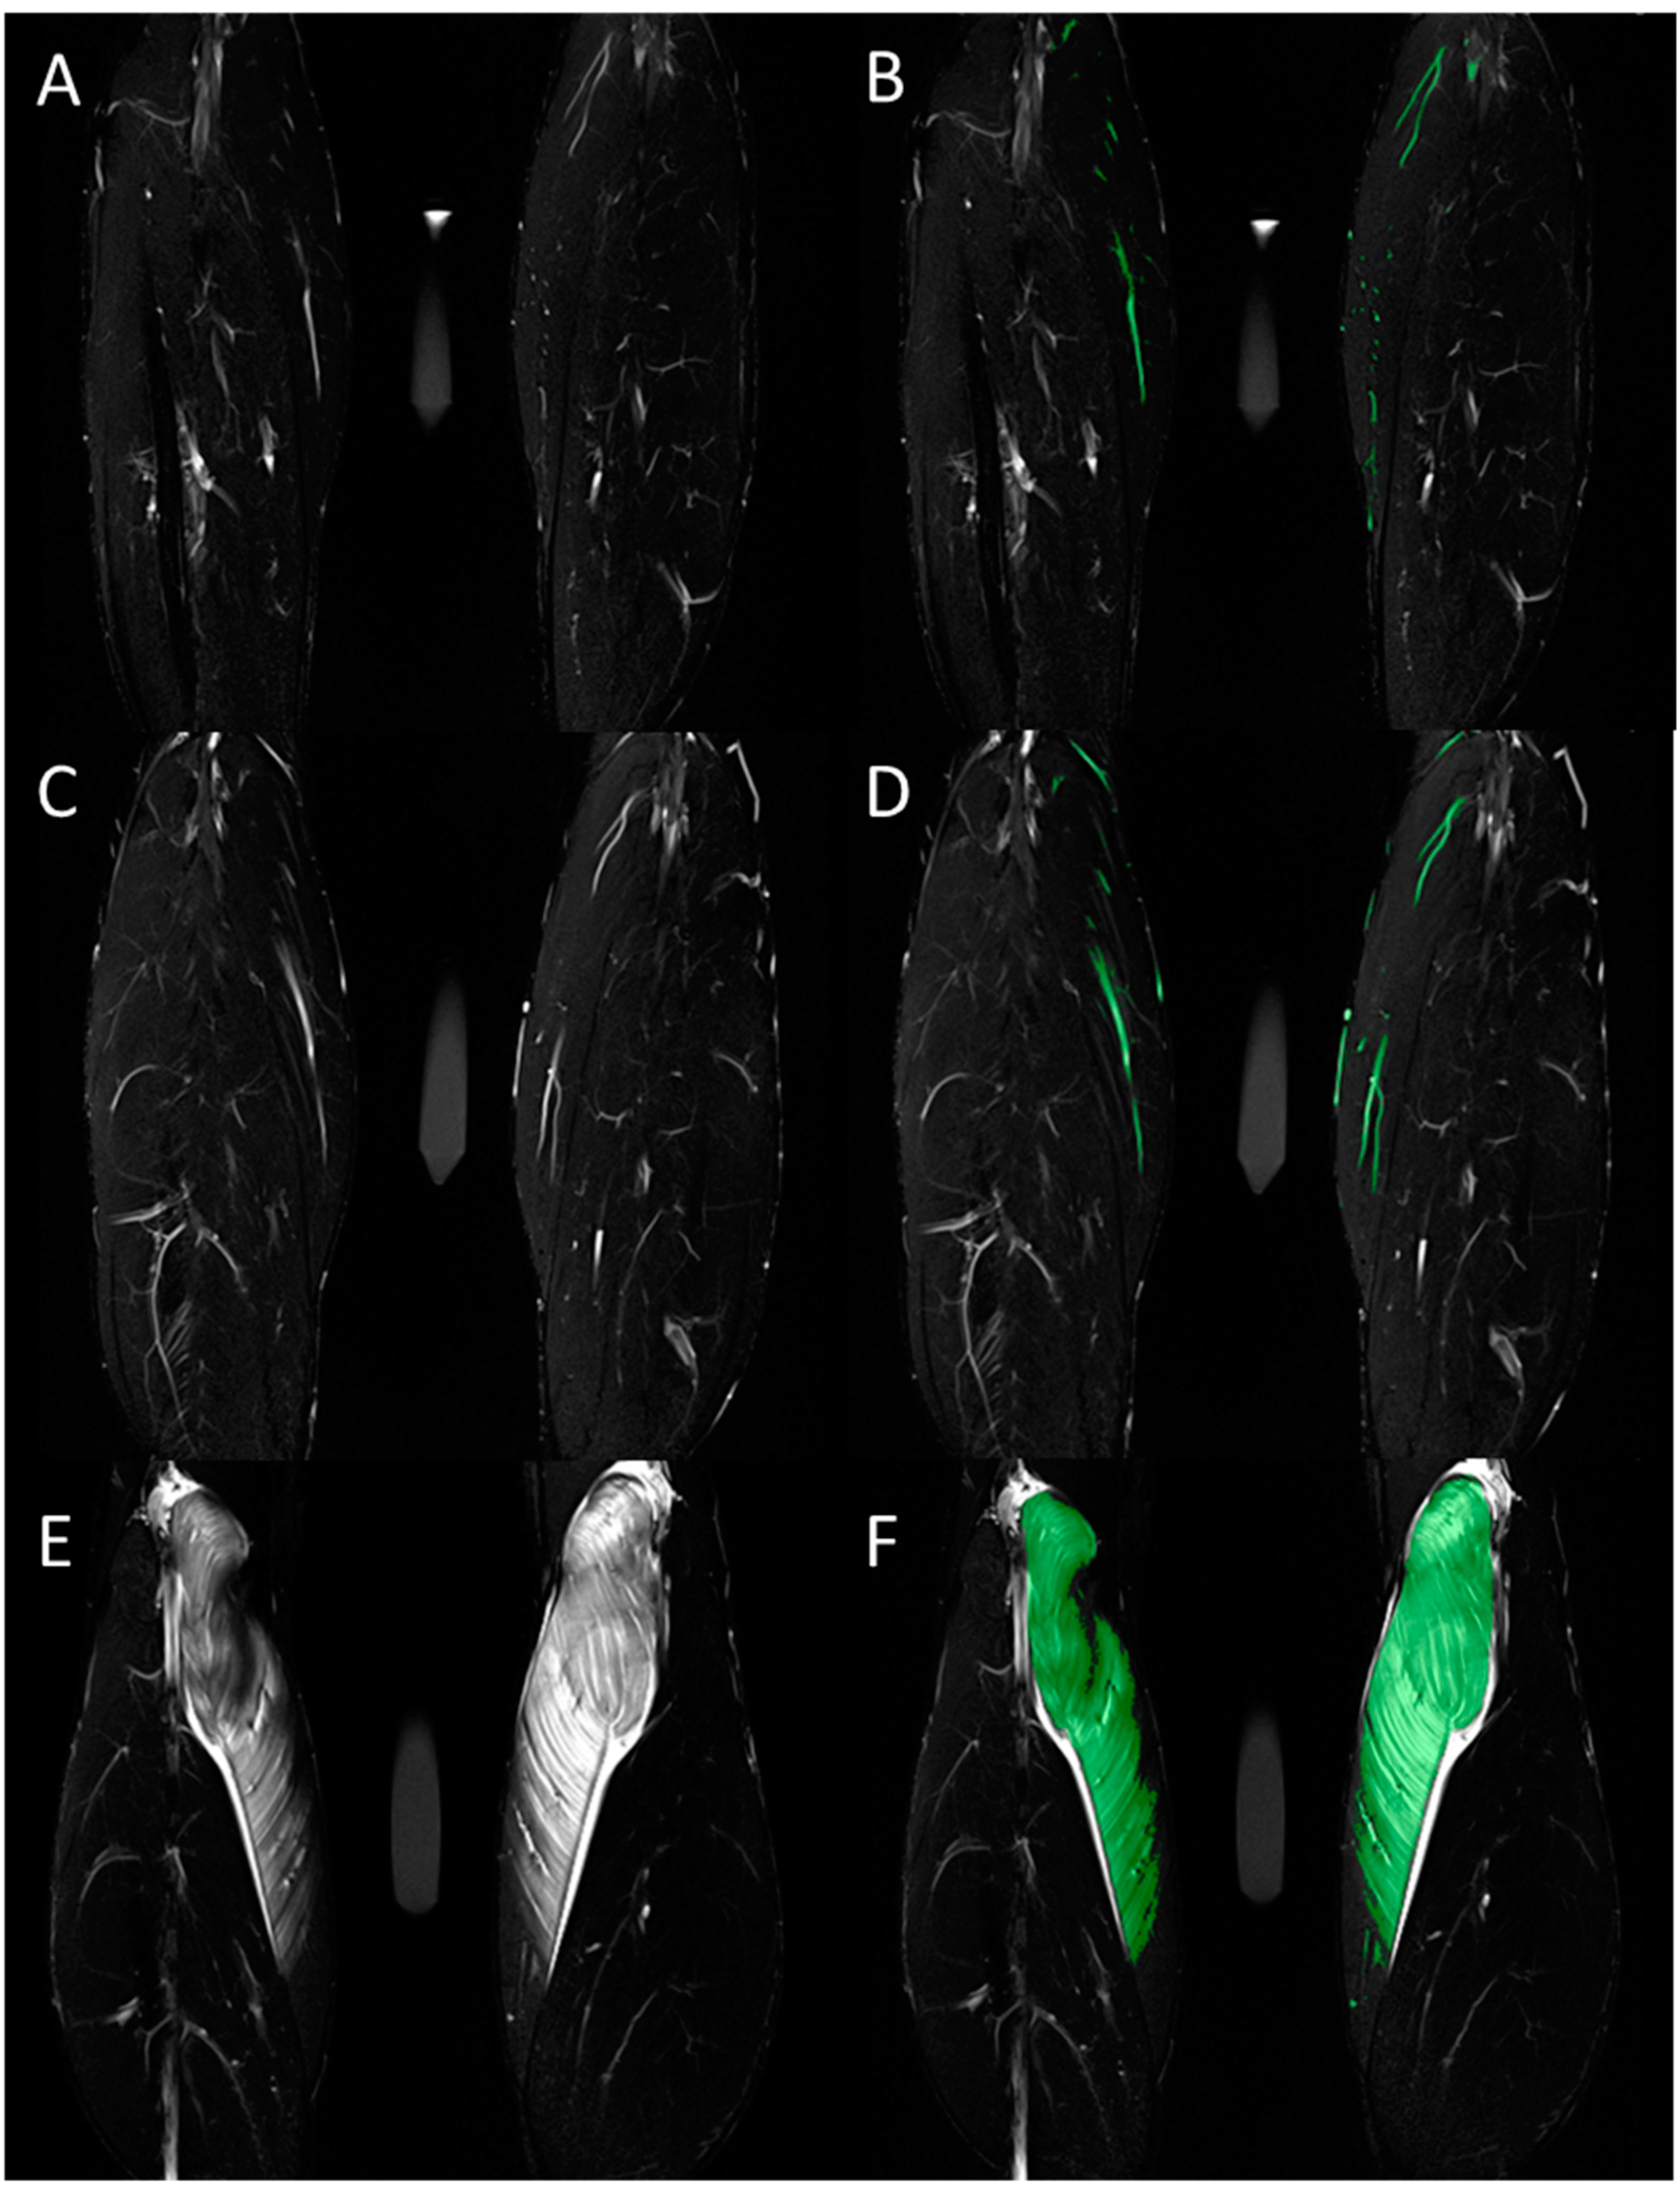

| T2 signal intensity | 30.5 ± 10.2 | 36.7 ± 14.5 | 76.2 ± 49.3 | 1.00 | 0.011 | 28.5 ± 13.1 | 32.4 ± 13.4 | 83.1 ± 70.2 | 1.00 | 0.005 | 1.00 | 1.00 | 1.00 |

| T2 relaxation time (ms) | 36.3 ± 3.3 | 39.1 ± 5.8 | 54.9 ± 23.8 | 1.00 | 0.007 | 36.3 ± 3.9 | 38.4 ± 5.5 | 57.7 ± 27.9 | 1.00 | <0.001 | 1.00 | 1.00 | 1.00 |

| Volume of edema (mL) | 12.1 ± 8.9 | 17.8 ± 11.0 | 106.4 ± 108.9 | 1.00 | 0.003 | 15.4 ± 13.0 | 18.3 ± 20.9 | 117.9 ± 135.0 | 1.00 | 0.025 | 1.00 | 1.00 | 1.00 |